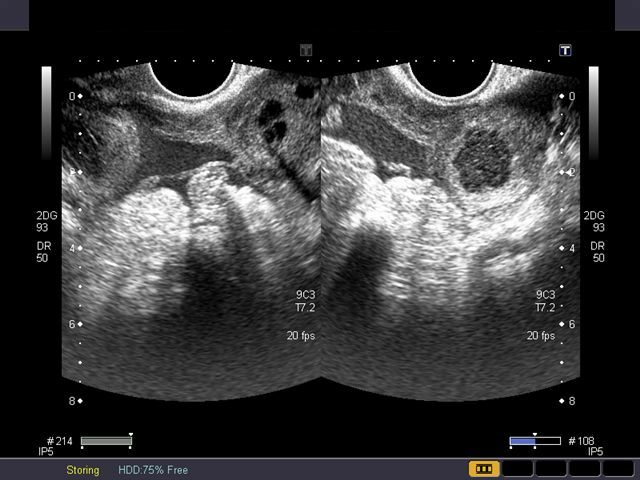

அதிலும் ‘அல்ட்ரா சவுண்ட்’ எனும் பரிசோதனைக் கருவியின் கண்டுபிடிப்புக்குப் பின், இந்தக் கட்டி உள்ளதை உடனடியாகப் பார்க்க முடிவதால், இதன் தோற்றத்தையும் வளர்ச்சியையும் தெளிவாகக் கவனித்து சிகிச்சை கொடுக்க முடிகிறது.

மகப்பேறு மருத்துவர் கர்ப்பிணியின் வயிற்றைத் தொட்டுப் பரிசோதிக்கும்போது, கர்ப்ப நாட்களுக்கு அதிகமாக வயிறு பெரிதாக இருப்பதாக உணர்ந்தால், சந்தேகத்தின் பேரில் அல்ட்ரா சவுண்ட் ஸ்கேன் பரிசோதனையை மேற்கொள்ளச் சொல்வார். அதில் ‘நார்த்திசுக் கட்டி’ இருப்பது தெரியும்.

கட்டி எந்த இடத்தில் உள்ளது, அளவு என்ன, எத்தனை கட்டிகள், பிரசவத்துக்குத் தொந்தரவாக இருக்குமா என பல தகவல்களை அதில் தெரிந்துகொள்ள முடியும். அதற்கேற்ப கர்ப்பிணிக்குத் தேவையான சிகிச்சை முறைகளைத் தேர்வு செய்துகொள்ள முடியும்.

கர்ப்பிணியின் முதல் செக்கப்பில் அல்ட்ரா சவுண்ட் ஸ்கேன் பரிசோதனையில் தெரியும் இந்தக் கட்டி, பெரும்பாலும் முதல் டிரைமெஸ்டரிலேயே கரைந்துவிடும். அதனால், இந்தக் கட்டி குறித்து பயப்படத் தேவையில்லை. இரண்டாம் டிரைமெஸ்டரில் மீண்டும் ஒருமுறை ஸ்கேன் செய்து இதை உறுதி செய்துகொள்ள வேண்டும்.

சினைப்பையில் ஏற்படும் மற்ற கட்டிகளும் ஆரம்பத்தில் எவ்வித அறிகுறியையும் வெளிக்காட்டுவதில்லை. ஸ்கேன் பரிசோதனையில் மட்டுமே அவை தெரியும் அல்லது போகப்போக அடிவயிறு பெரிதாகத் தெரியும்.